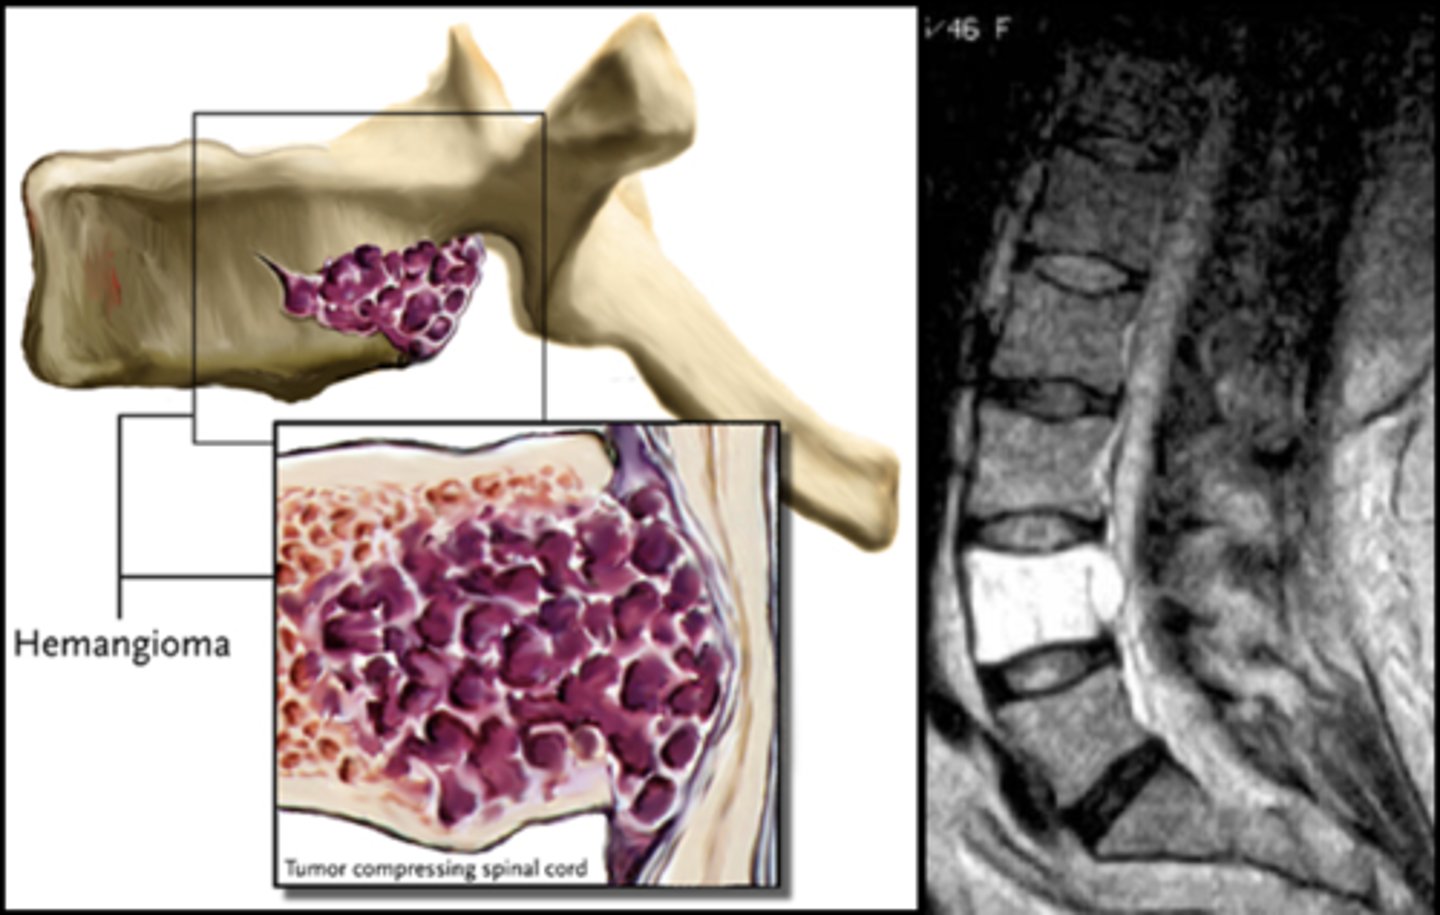

Vertebral hemangioma

- Solitary vascular neoplasm

- Slow growing

<p>- Solitary vascular neoplasm</p><p>- Slow growing</p>

- 2-3% of all spine tumors (radiographs)

- 11% of all spines (autopsy)

- Most common benign tumor of the spine

State the incidence of vertebral hemangioma

- First seen over 40 y.o.

- F>M

- Most asymptomatic

- 75% in spine and skull

- Lower thoracic and upper lumbar

- Vertebral body

• Extension into vertebral arch (10-15%)

State the clinical features of vertebral hemangioma

- Vertical striations (corduroy cloth)

- Expansion (rare) may result in neurologic findings

- Skull ("sand dollar")

- Paravertebral swelling

State the radiographic features of vertebral hemangioma

<p>State the radiographic features of vertebral hemangioma</p>

Expansile

_____ vertebral hemangioma

<p>_____ vertebral hemangioma</p>